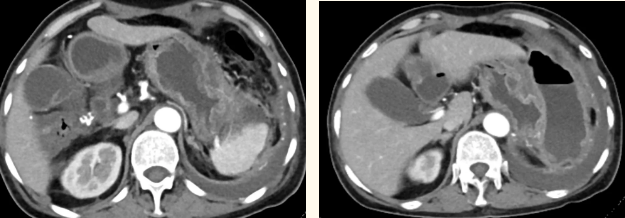

一籌莫展的她終于在病友的介紹下,來到西安國際醫(yī)學(xué)中心醫(yī)院找到蔡磊主任。經(jīng)過詢問病史,查體等,蔡磊主任建議口服索坦治療。3個月后,李阿姨復(fù)查CT提示胃間質(zhì)瘤較前明顯縮小,大小約10.4cm?6cm。但仍存在消化道出血,營養(yǎng)狀況差,全身無力,骨髓抑制。蔡磊主任隨即將患者收治入院。